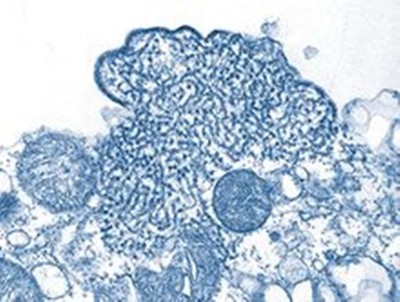

New York: A new coronavirus “variant of interest” named Mu – also known by its scientific name as B.1.621 – is being closely monitored by the World Health Organization (WHO), the agency has said.